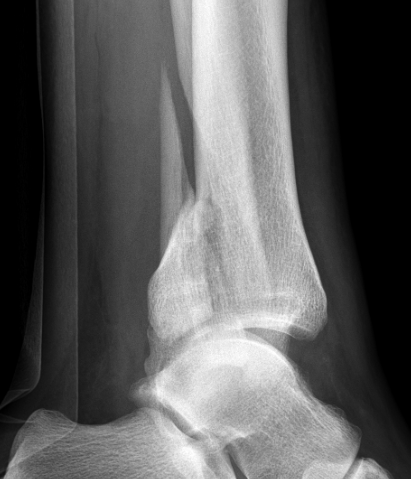

| Bimalleolar fractures | Trimalleolar fractures |

Fibular + medial malleolus Fibular + posterior malleolus |

Fibular + Medial malleolus + Posterior malleolus |

Bimalleolar fractures

Medial malleolus + Weber B lateral malleolus

Medial malleolus + Weber C lateral malleolus

Tri-Malleolar Fracture

Lateral malleolus + medial malleolus + posterior malleolus